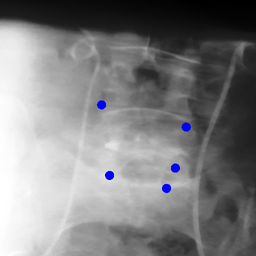

The dataset we use in the experiments is a cone-beam CT (CBCT) dataset captured for radiation therapy. The dataset contains 340 raw CBCT scans with each has 780 X-ray images. Each X-ray image comes with a geometry file that provides the registration ground truth as well as the information to reconstruct the CBCT volume. Each CBCT volume is reconstructed from the 780 X-ray images, and in total, we have 340 CBCT volumes (one for each CBCT scan). We use 300 scans for training and validation, and 40 scans for testing. The size of the CBCT volumes is 448×448×768448448768448\times 448\times 768 with 0.5 mm voxel spacing, and the size of the X-ray images is 512×512512512512\times 512 with 0.388 mm pixel spacing. During the experiments, the CBCT volumes are treated as the 3D pre-intervention data, and the corresponding X-ray images are treated as the 2D intra-intervention data. Sample X-ray images from our dataset are shown in Figure. Note that unlike many existing approaches [15, 17, 25] that evaluate their methods on small datasets (typically about 10 scans) which are captured under relatively ideal scenarios, we use a significantly larger dataset with complex clinical settings, e.g., diverse field-of-views, surgical instruments/implants, various image contrast and quality, etc.

We consider two common views during the experiment: the anterior-posterior view and the lateral view. Hence, only X-rays that are close to (±5°plus-or-minus5°\pm 5\degree) these views are used for training and testing. Note that this selection does not tightly constrain the diversity of the X-rays as the patient may be subject to movements with regard to the operating bed. To train the proposed method, X-ray and DRR pairs are selected and generated with a maximum of 10°10°10\degree rotation offset and 202020 mm translation offset. We first invert all the raw X-ray images and then apply histogram equalization to both the inverted X-ray images and DRRs to facilitate the similarity measurement. For each of the scan, we also annotate their landmarks on the reconstructed CBCT volume for further evaluation.

Refer to caption

Figure 6: Sample raw X-ray images of our dataset.